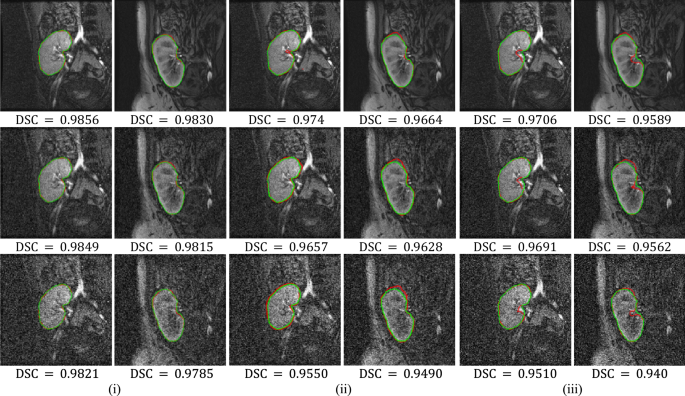

It is clear from Table 3 that the BCDU-Net model performs notably better than the original U-Net model. However, the FML method performs best on segmenting kidneys from high and low-contrast images. In particular, the mean and standard deviation of HD95 metric reveal that our method is more than 15 × accurate and about 20 × more consistent than the original U-Net model. Moreover, it is about 7 × accurate and 10 × consistent than the BCDU-Net model. To further demonstrate the efficiency of the FML method over the deep models, we apply the three methods to automatically segment the kidney from a set of noisy images. The noisy images are artificially generated by adding Gaussian noise with zero mean and variance values equal 0.01 and 0.05 (note the images are already normalized to range [0, 1]). Figure 5 visually compares between the three methods.

Comparison between the FML method vs U-Net and BCDU-Net models on noisy DCE-MRI images. Segmentation results are shown in red for the FML method in (i), U-Net model in (ii), and BCDU-Net model in (iii). The ground-truth segmentations are shown in green, with DSC reported beneath each result. First row shows original images, second row shows images with noise variance 0.01, and third row shows images with noise variance 0.05.

Clearly the performance of the FML method on noisy images is more stable and accurate than those of the U-Net and BCDU-Net models. The improvement is more profound on images with higher noise levels. It is important to mention that the FML method is easier to explain its behavior and interpret its results compared to the deep models. For example, obtaining rather a noisy kidney contour from the segmentation result would suggest increasing the weighting factor \({\uplambda }_{1}\) or \({\uplambda }_{3}\) or both in our method as a corrective action.